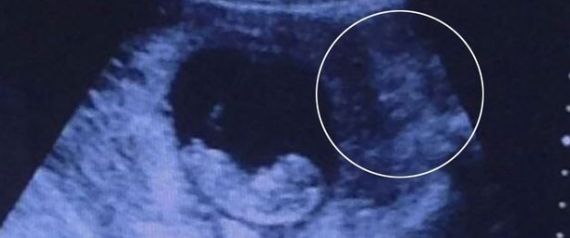

شاهد صورة مرعبة لـ"شيطاناً" يراقب جنيناً في فحص الموجات فوق الصوتية